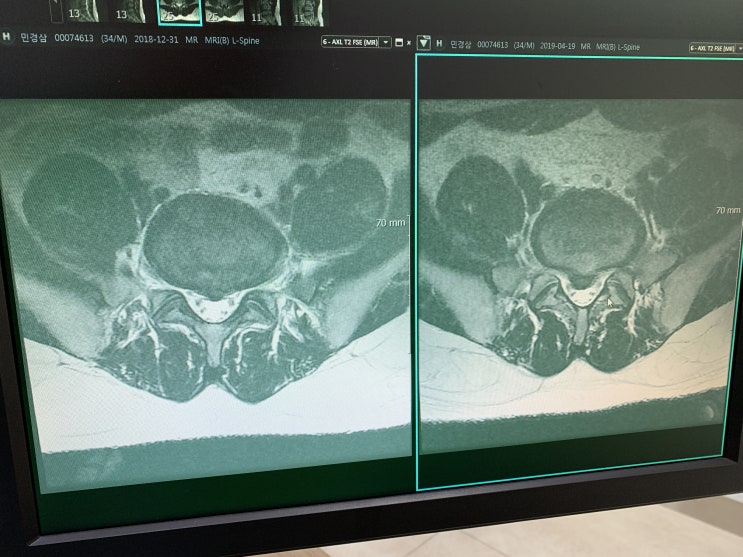

허리디스크 수술 두번 다시 경험 하고 싶지 않은 날

분명 2019년 1월에 시술을 하고서 시술결과가 너무 좋아서 열심히 재활하면서 생활 했는데.... 너무 ...